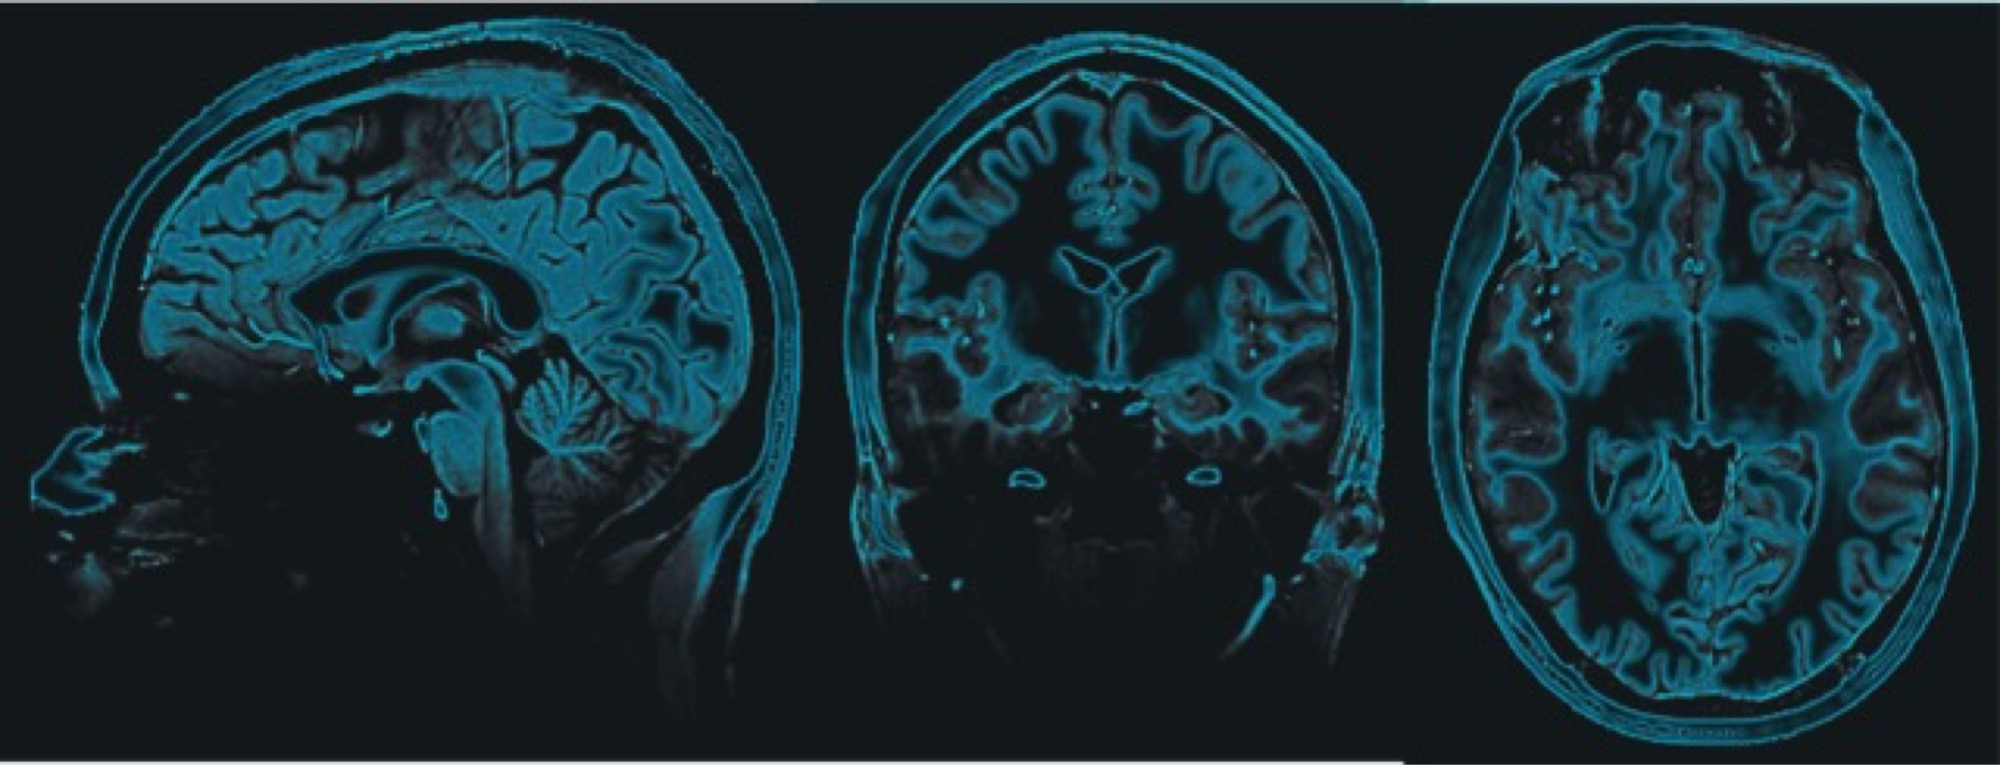

The Rideaux Lab is a research group that studies design principles of the brain, with the aim to understand their role in psychopathology and how they can be used to advance artificial intelligence.

The Rideaux Lab is dedicated to advancing the understanding of neural sensory processing in health and disease, and the application of discoveries in biological systems to improve the scope and effectiveness of artificial intelligence.

Our group focuses on exploring the foundations of brain function, investigating the neural underpinnings of neurological disorders and leverages these insights to advance artificial intelligence systems and more effective tools for interpreting neural signals.